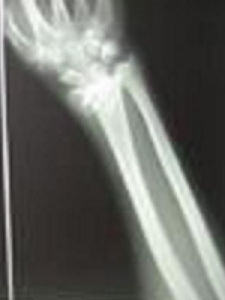

Colles骨折系指發生於橈骨遠端的松質骨骨折,且向背側移位者而言。

X線片上,典型的錯位表現為以下幾點:

1.橈骨遠端骨折塊向背側移位;

2.橈骨遠端骨折塊向橈側移位;

3.骨折處向掌側成角;

4.橈骨短縮,骨折處背側骨質嵌入或粉碎骨折;

5.橈骨遠端骨折塊鏇後。

以上的錯位,組成一典型餐叉狀畸形,使得掌傾角及尺偏角減小或呈負角。

x線片上常見合併有尺骨莖突骨折,骨折的尺骨莖突不同程度的分離,嚴重者並向橈側移位。如無尺骨莖突骨折,而橈骨遠折端向橈側移位明顯時,說明有三角纖維軟骨盤的撕裂。